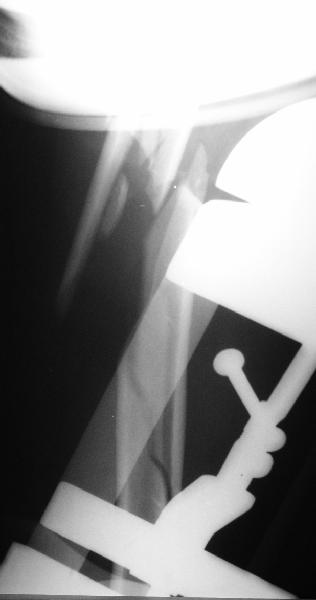

Although we can not see exactly the head piece, and assuming that there are not signs of infection, my suggestion would be to do some type of "bridging" procedure : implant fixation in head piece and distal main fragment, and the rest to be left on its soft tissue attachments (living bone graft).

I just did this attached case, using 90 degrees angled blade plate, and this would be my preference in all similar cases.

Good luck and send us your postoperative images, please. Sincerely,

Отправитель: Alexander Chelnokov 05 Октябрь 2003, 13:41

Well, to date he is still on abduction splint with traction applied to a wire placed through the olecranon. Images attached. The acetabulum

was ORIFed. The humerus is still discussing...